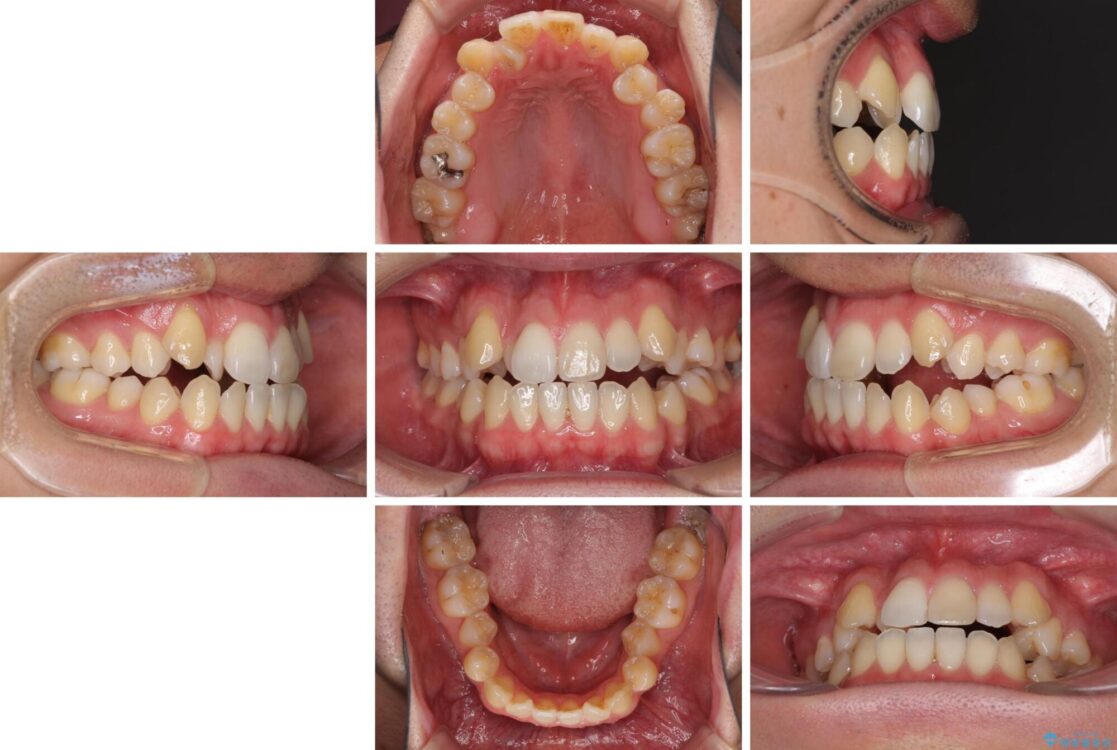

八重歯と前歯のデコボコを気にして来院された患者様です。

治療計画

営業職であり、商談などで飲食をする機会が多いとのことで、インビザラインではなく、ワイヤー装置にて矯正治療を行うこととしました。

治療前

• 左右の八重歯が気になる ワイヤー装置での咬み合わせ改善 治療前画像